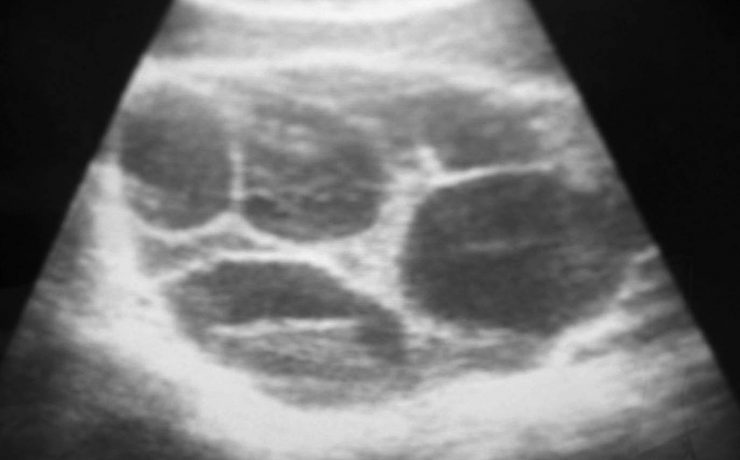

La litiasis vesicular

La litiasis vesicular se presenta hasta en el 20% de la población adulta, de estos hasta el 15% tienen coledocolitiasis. Sus factores de riesgo son: raza hispana, sexo femenino, edad mayor de 50 años, obesidad y perfil lipídico alterado. Su presentación clínica es el cólico